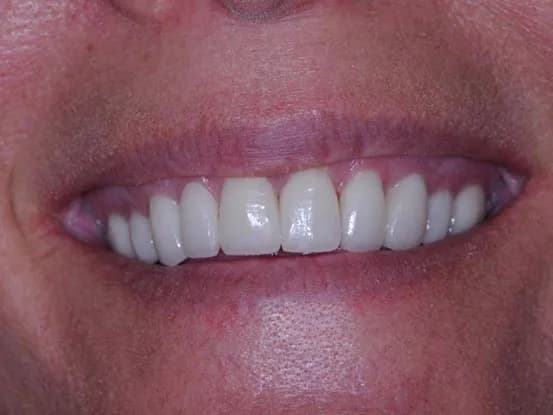

Case 1

26 year old female with teeth crowding and slight overbite. Patient refused to have 2 years of orthodontics. Gingivectomy, cosmetic bonding, extraction, Zoom Bleaching, and 12 units of e-max restorations performed.